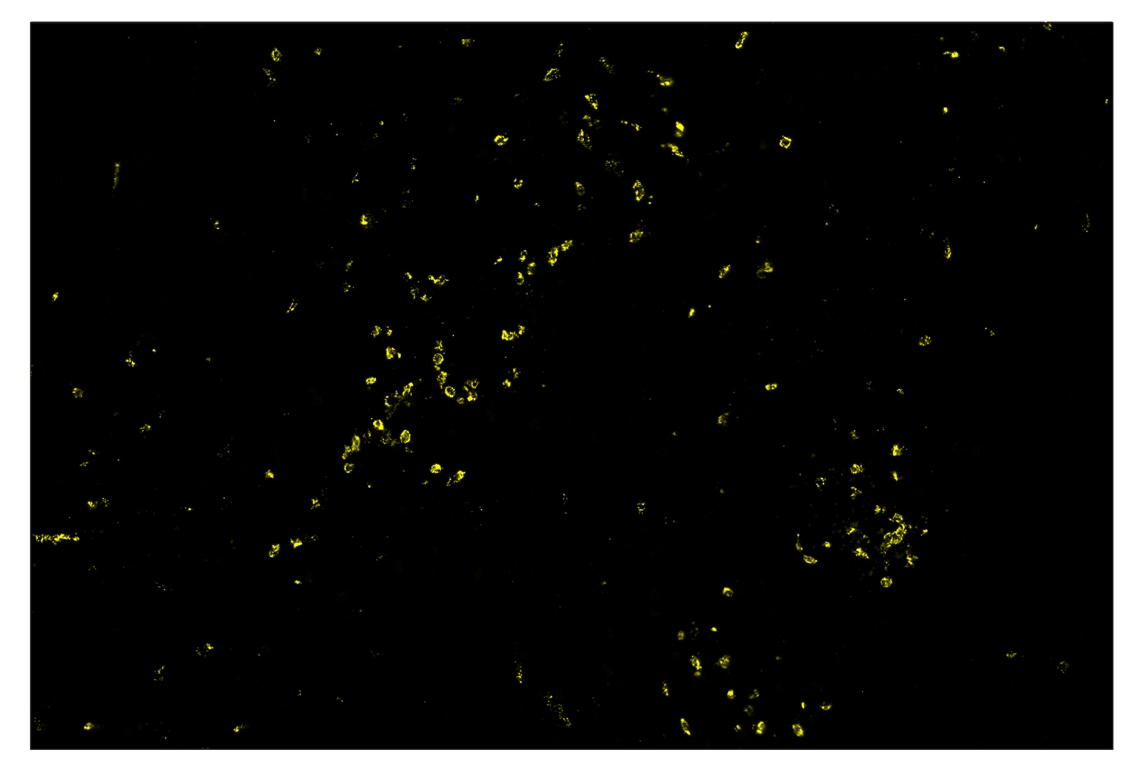

Immunohistochemistry Image 3: Myeloperoxidase (E1E7I) & CO-0138-750 SignalStar<sup>™</sup> Oligo-Antibody Pair

Orders: 877-616-CELL (2355) [email protected] Support: 877-678-TECH (8324) [email protected] Web: cellsignal.com